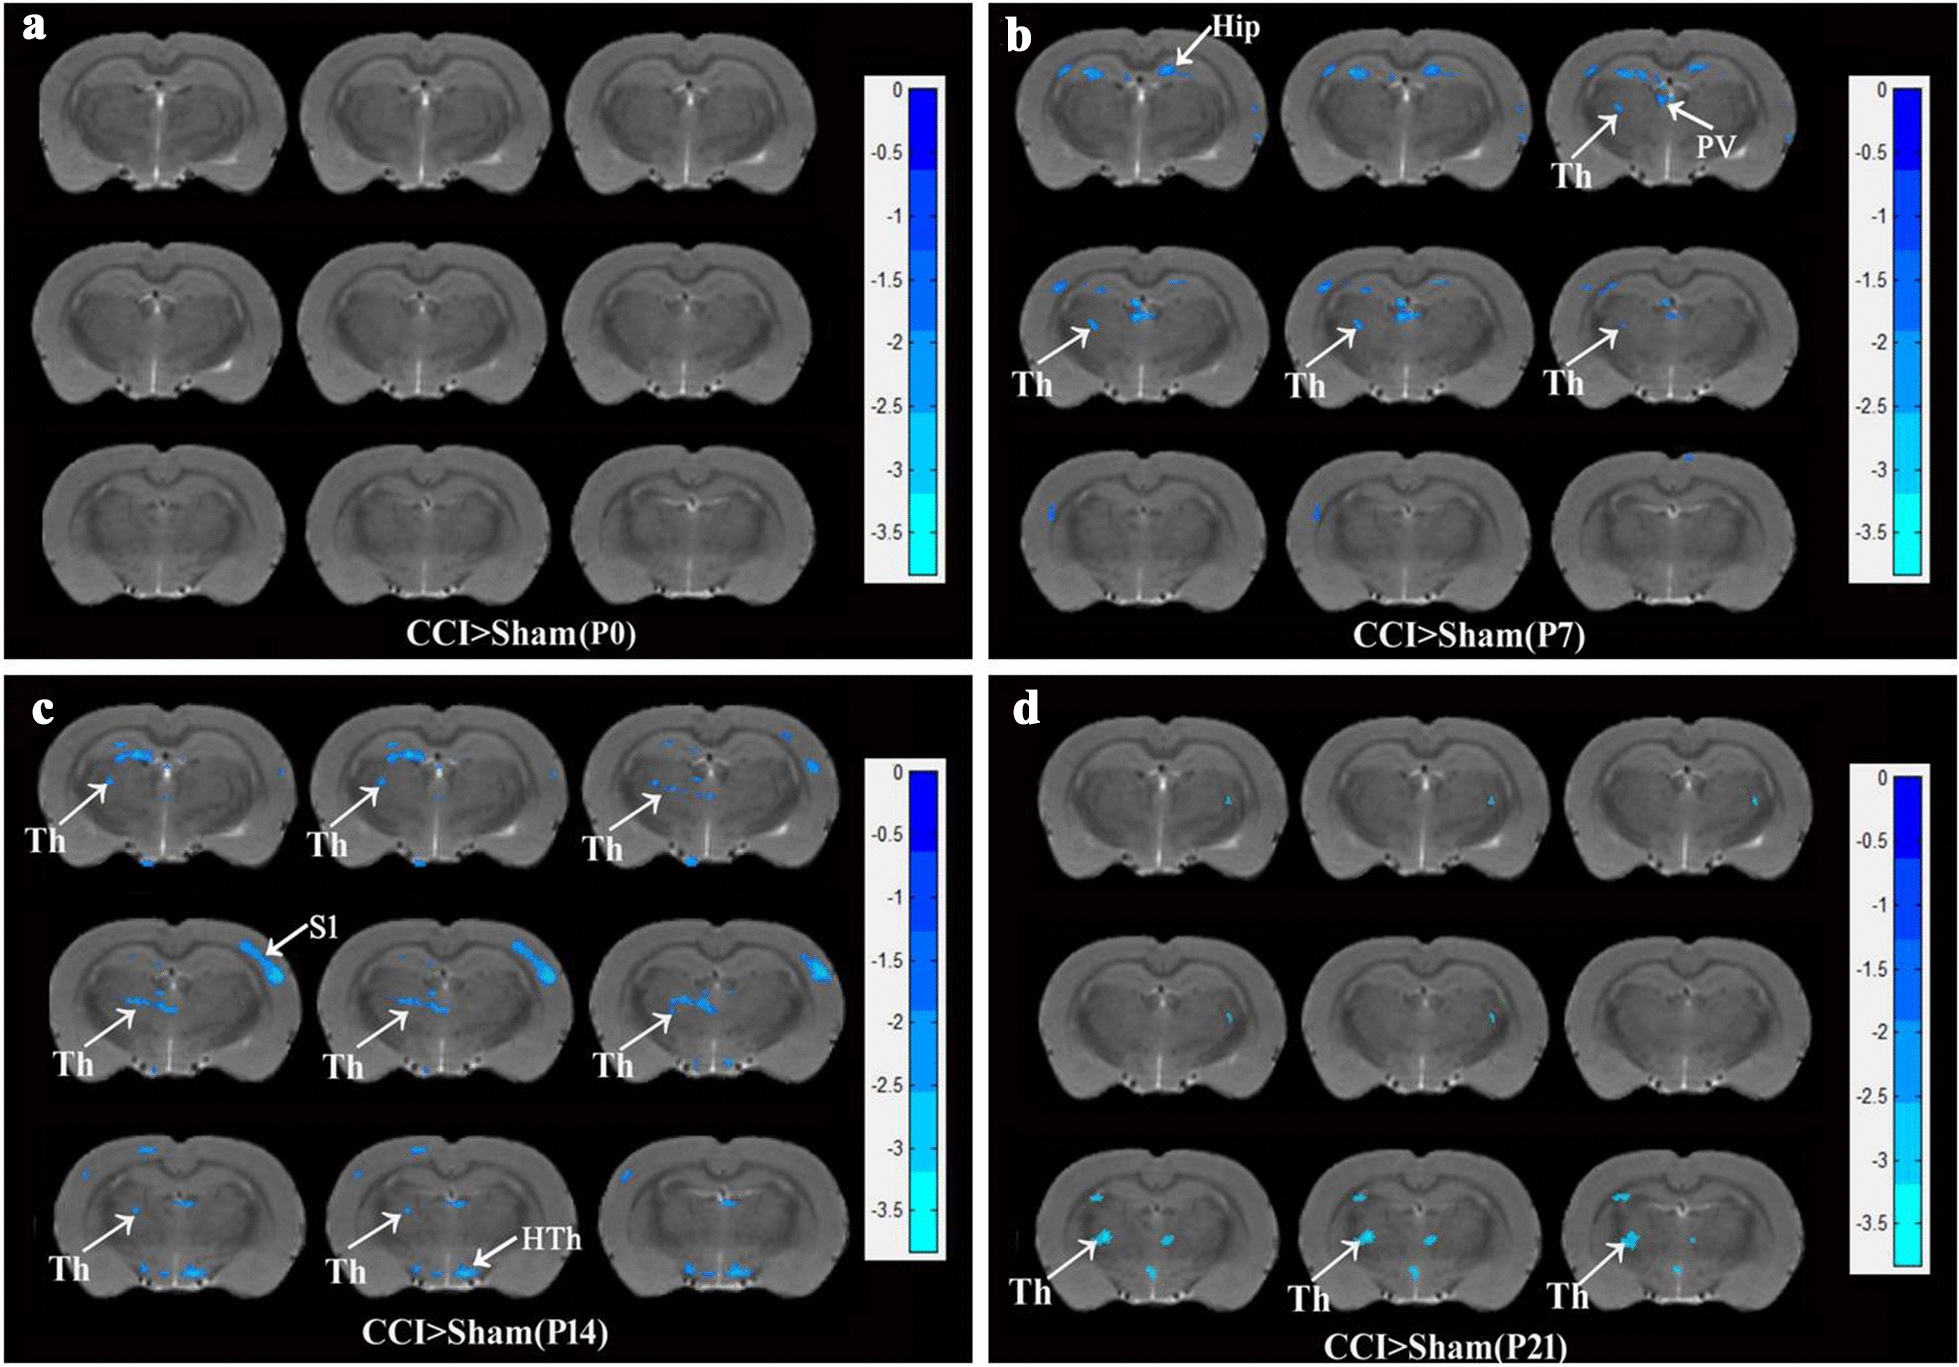

ReHo was applied to assess resting-state brain activity during the pain state. There were no statistic differences of ReHo between two groups on 0 days without surgery (Fig. 2a). As shown in Fig. 2b, compared to the sham group, decreased ReHo on the left side of the thalamus was found through MRI scanning on day seven after CCI surgery (P < 0.01). In addition to the thalamus, decreased ReHo in the bilateral hippocampus and left paraventricular nucleus (PV) of the thalamus were also observed on day 7 after CCI surgery. As shown in Fig. 2c, compared to the sham surgery condition, decreased ReHo on the left thalamus and the right primary sensory cortex (S1) and Hypothalamus (Hth) was found on day 14 after CCI surgery (P < 0.01). As shown in Fig. 2d, compared to sham surgery rats, decreased ReHo was found mainly on the left side of the thalamus on day 21 after CCI surgery (P < 0.01).

Fig. 2.

Thalamus and other brain areas ReHo detection in the time course of CCI rats compared with Sham rats. a ReHo levels were measured with fMRI on day 0 before surgery between two groups (Sham, n = 10; CCI, n = 9). b ReHo on day 7 after surgery. c ReHo on day 14 after surgery. d ReHo on day 21 after surgery. The coronal section position of thalamus was the range from Interaural 6.36 mm, Bregma − 2.52 mm to Interaural 5.88 mm Bregma − 3.12. CCI-induced Reho decrease compared with the sham group, two-way repeated ANOVA, F1, 51 = 221.08, P < 0.001, post hoc Tukey test: P < 0.01